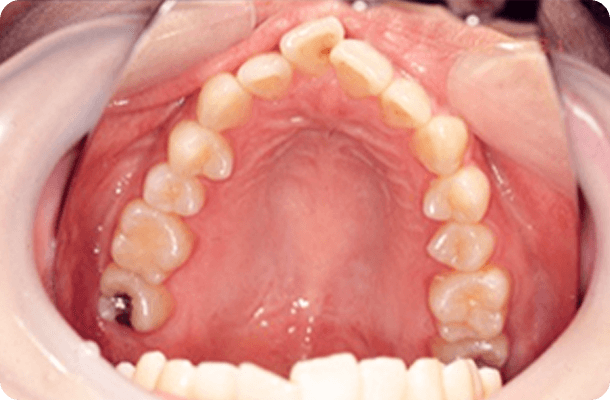

治療後の写真

(IPR)余地を作った後配列して

9ヶ月後、治療終了。